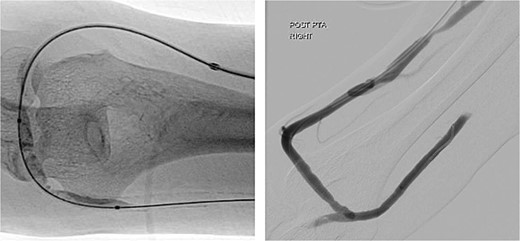

The harvested vein was tunnelled between the proximal radial artery (at the brachial bifurcation) and the elbow segment of the AVF. The AVF was then ligated at the anastomosis. A thrill was well felt in the upper arm after the procedure (Fig. 4).

Post-operatively, all symptoms of ischaemia resolved (Fig. 5). The patient’s pulses were restored and dialysis resumed without complications. A gentle angioplasty of the conduit vessel was performed 1 month later to maintain access flow (Fig. 6). The access site remained functional at the 12-month follow-up.